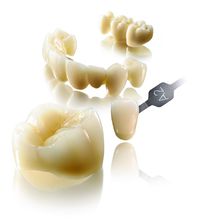

二、全瓷修复

全瓷修复是无金属瓷修复的统称,修复体不再使用金属,而采用与牙齿颜色相近的高强度瓷材料制成,因此较金属基底烤瓷修复体更美观,半透明度与天然牙近似,修复后牙龈边缘表现更加自然,可达到仿真效果,且具有对周边组织无刺激等优点,已被广泛用于临床。全瓷修复弥补了金属烤瓷技术的诸多缺陷,且具良好的牙齿美容功效。

全瓷修复比传统修复的优势在于:

4、色泽形态逼真,咀嚼功能、稳固性都非常接近真牙。不会出现崩瓷、黑线等现象。